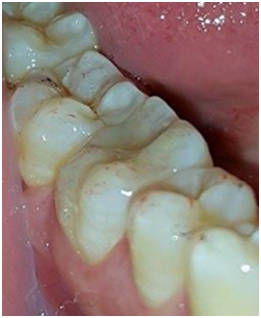

A 25years old male patient with unremarkable medical history, presented to the department of fixed prosthodontics with esthetic and functional demand. His chief complaint was to replace the defective amalgam restoration on the first right mandibular molar (Figure 1). A comprehensive clinical examination revealed good hygiene, a defective amalgam restoration on the first right mandibular molar, which caused a papilla inflammation between the 46 and the 47.

Figure 1 Defective amalgam restoration on the first right.